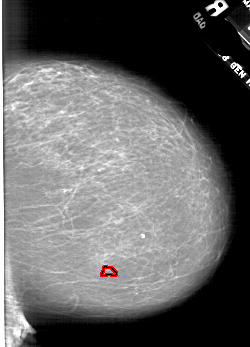

A_1773_1.LEFT_MLO

LEFT_MLO LINES 6586 PIXELS_PER_LINE 3916 BITS_PER_PIXEL 12 RESOLUTION 43.5 NON_OVERLAY

FILE: A_1773_1.RIGHT_MLO.OVERLAY

TOTAL_ABNORMALITIES 1

ABNORMALITY 1

LESION_TYPE CALCIFICATION TYPE PLEOMORPHIC DISTRIBUTION CLUSTERED

ASSESSMENT 4

SUBTLETY 2

PATHOLOGY BENIGN

TOTAL_OUTLINES 1

BOUNDARY